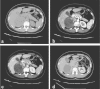

Presentation of case: We report the clinical case of a 49 years-old woman who came to our observation with aspecific abdominal pain. A computed tomography (CT) abdominal scan revealed a 11cm right adrenal mass. This lesion was well circumscribed, round, encapsulated. After iodinated-contrast we observed a progressive, inhomogeneous enhancement without evidence of active bleeding and with pre-operative diagnosis of adrenal hemangioma. Laparoscopic adrenalectomy was performed by a transperitoneal flank approach. Pathological examination revealed a 11cm adrenal mass with extensive central necrotic areas mixed to sinusoidal dilation and fibrotic septa. Postoperative diagnosis was adrenal hemangioma.